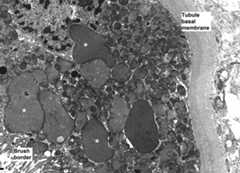

Electron microscopy revealed abnormal mitochondria in almost all cases (Figure 1). Some were greatly increased in size, while others appeared shrunken. They were usually grouped within the cell. Some epithelial cells showed marked mitochondrial depletion. Mitochondrial cristae could be absent or less abundant than normal, sometimes grouped at one pole of the mitochondria.

Figure 1.

TDF-induced epithelial cell dysfunction is due to mitochondrial damage. Enlarged mitochondria (*) are visible adjacent to normal-size mitochondria (+). Large mitochondria appear devoid of cristae, while other mitochondria show normal cristae content. When cristae are visible in dysmorphic mitochondria, they are usually grouped at a pole. (Original magnification ×8000.) Photograph kindly provided by Leal C. Herlitz, MD, Department of Pathology, Columbia University Medical Center in New York, New York.